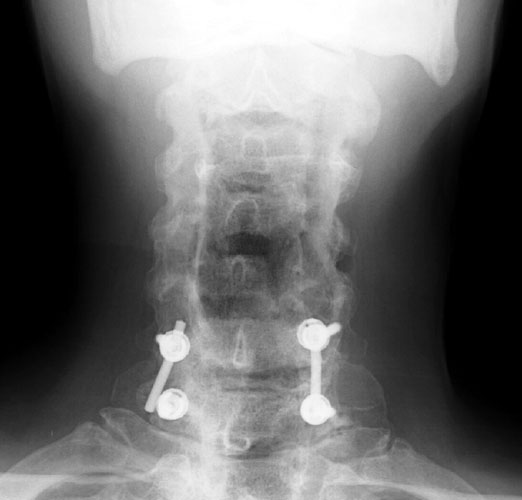

65 y.o male with prior surgery 23 years ago, secondary to trauma involving C4-5, C5-6 ACDF procedures. Now is 1 yr s/p bilateral C5 and C6 foraminotomy and C6-C7 posterior fusion and right iliac crest bone graft for persistent numbness and tingling f or 2 years.

3 months later, follow-up films show the posterior fixation at C6-7. Now noted that the screw at C7 has slipped off the support rod on the right.